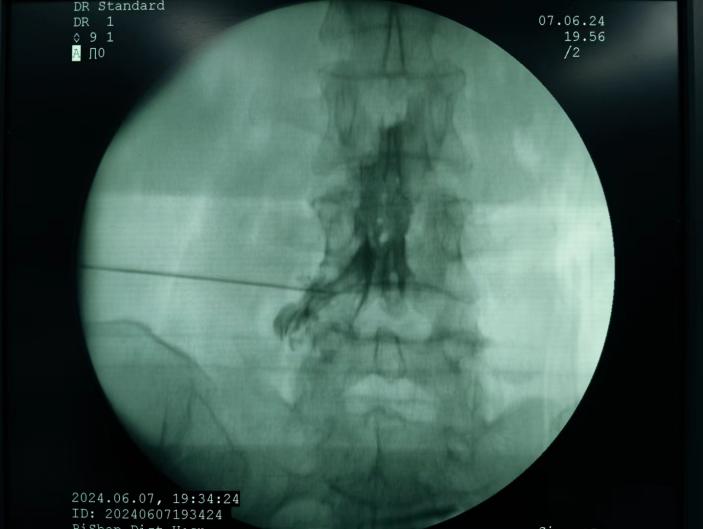

椎間盤射頻消融術、膠原酶椎間盤化學消融術